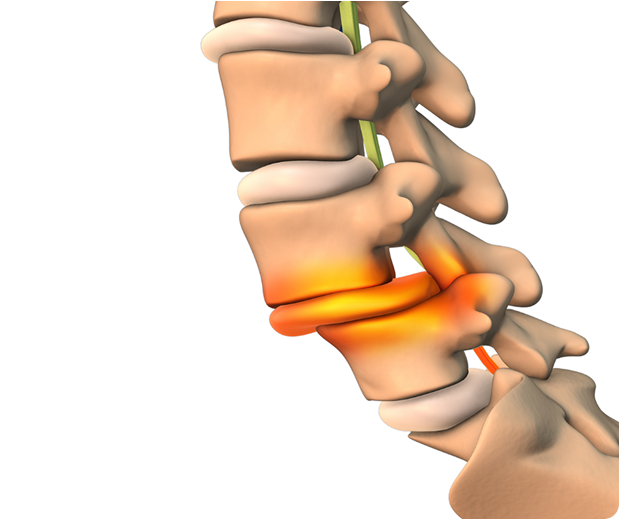

Degenerativna spondilolisteza je stanje hrbtenice, pri katerem eno vretence zdrsne naprej pred vretence pod njim.

Razlog pojava so degeneracijske spremembe kot posledica oslabitve medvretenčnih ploščic, ki ne zagotavljajo več potrebne stabilnosti hrbtenici.

Hrbtenica je sestavljena iz vretenc, ki so postavljena drug na drugega tako, da tvorijo stolp. Ko se eno izmed vretenc premakne, se zmanjša stabilnost celotne strukture. Zaradi premika se stisnejo ostale strukture, med njimi tudi živčna vlakna, kar povzroči povečanje bolečine. Težava, ki se pojavlja pogosteje pri ženskah, se imenuje spondilolisteza.

Hrbtenica je sestavljena iz diska spredaj in parnih fasetnih sklepov zadaj.

Disk deluje kot amortizer med vretenci, fasetni sklep pa omogoča upogibanje hrbtenice naprej (fleksija) in nazaj (ekstenzija).

S staranjem se disk "zmehča" in vretenca med seboj niso več tako trdno povezana, hkrati pa fasetni sklep ne zmore zadržati obsega giba. Postane šibkejši in dovoli preveč upogiba, kar omogoči, da eno eno vretence zdrsne naprej na drugo.